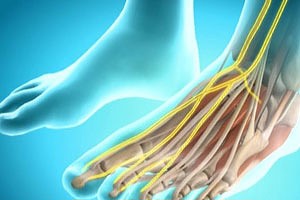

- Сбои в сосудистой и лимфатической системах. Повреждение провоцирует постоянный отек в конечности. Жидкость скапливается вокруг неподвижного сустава, давит на нервные окончания.

- Плохая эластичность связок, хрящей препятствует безболезненным движениям во время ходьбы.

Независимо от типа травматического повреждения наблюдается появление отечности, спровоцированной повреждением капилляров, функциональная обязанность которых — обеспечение обменных процессов между кровью и тканями.